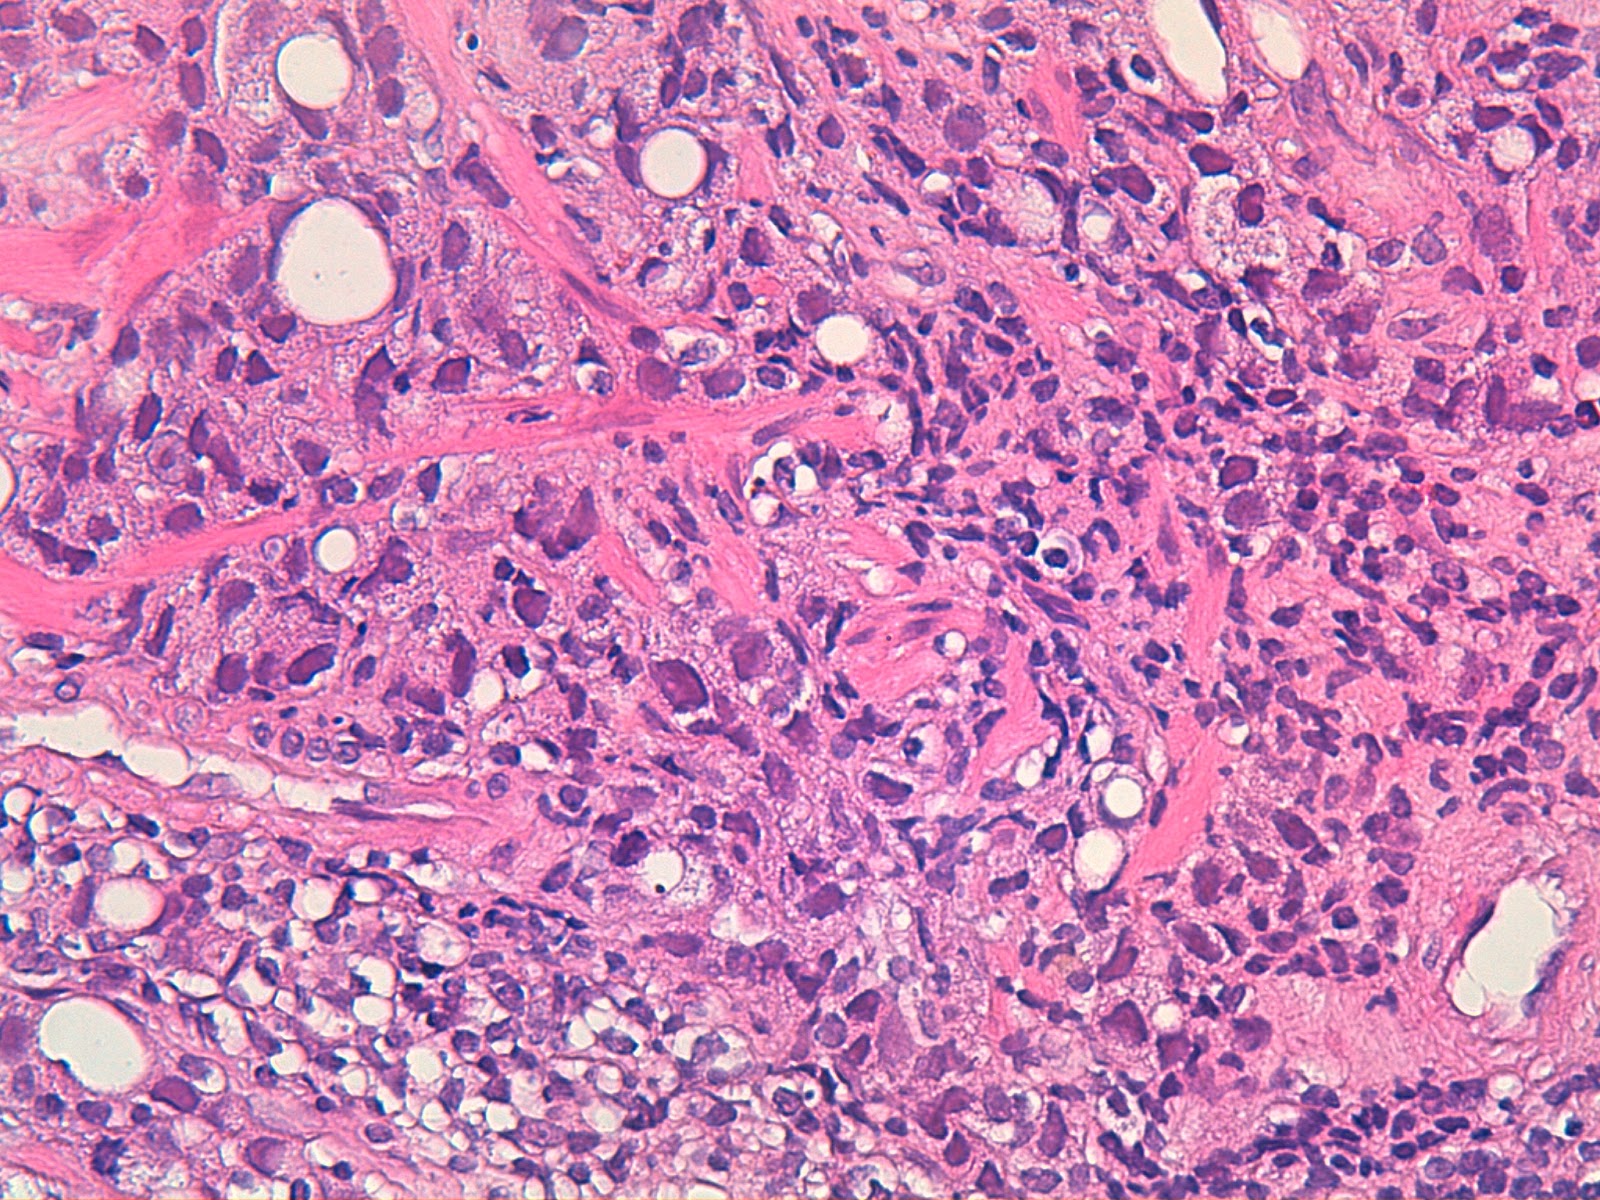

Adenocarcinoma de prostata .

Prostate Cancer: Grading .

patologica.com: Nuevos grados histológicos para el ... .